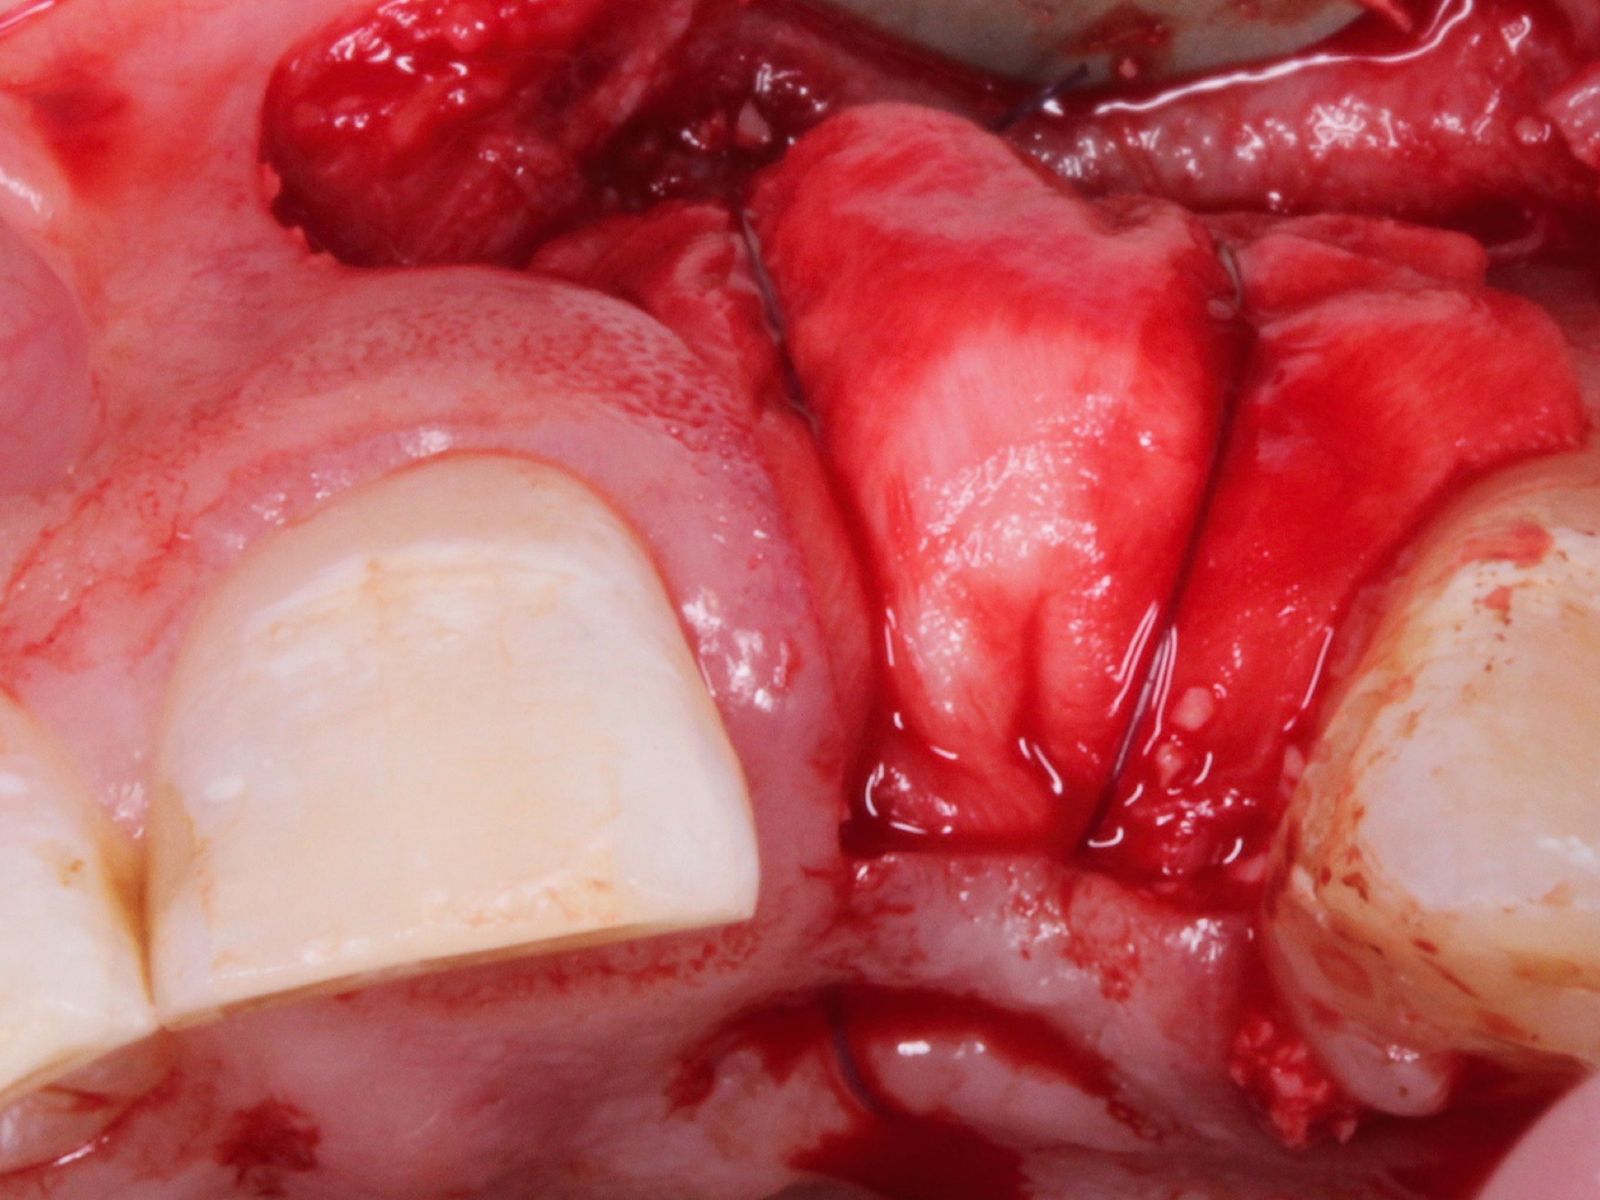

- Understand the principles of graft harvesting and management of the recipient and donor sites

- Practical application of site augmentation, including graft harvesting and managing recipient and donor sites - Use of Ossix Bone, Ossix Plus and Ossix Volumax

- Recognise, manage and prevent complications associated with soft tissue grafting

- Understand basic and advanced suturing techniques

This course will teach you the fundamentals of soft and hard tissue grafting. Beginning with a brief revision of the periodontium, you will then learn how to identify patients who would benefit from such surgeries, as well as safe and effective ways to manage them. This includes suture technique and flap design, soft and hard tissue graft materials with specifications on the qualities and handling of each, and post-procedural management. Medico-legal advice and managing complications will also be discussed to help you gain a comprehensive view of this field.